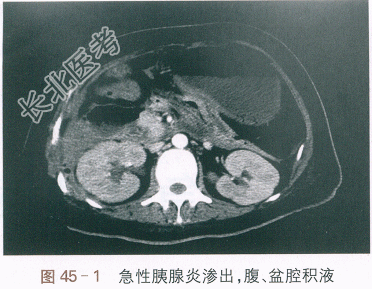

- [材料题] 患者,女性,38岁,因“中上腹痛伴恶心呕吐发热3天”入院。患者入院前3天进食油腻食物后出现中上腹刀割样疼痛,持续性加重,放射至后背部;伴恶心、呕吐,呕吐物为胃内容物。6h后出现发热,体温达38.8℃。至当地医院就诊,当时查血淀粉酶:320IU/L;血常规示:WBC 18.2×10⁹/L,N91.2%,Hb 125g/L,PLT 234×10⁹/L。腹部超声提示:胆总管毛糙,胰腺形态增大,考虑急性胰腺炎。当地医院予禁食、胃肠减压、补液等治疗后,患者恶心呕吐好转,但中上腹痛持续加重,无排便,体温持续升高。为进一步诊治收住入院。既往史:6年前因急性胆囊炎行腹腔镜下胆囊切除术,13年前剖腹产史,16年前阑尾切除术史。高血脂病史6年,甘油三酯和胆固醇均升高。无大量饮酒史及特殊药物使用史,无药物过敏史。体格检查:T39.4℃,BP110mmHg/72mmHg,R32次/min,P108次/min,神志清,精神差,急性病面容,体型肥胖,全身皮肤巩膜无黄染,HR108次/min,律齐,未及早搏和杂音,呼吸急促,双肺呼吸音减低,左下肺呼吸消失,未及明显干湿啰音。腹部轻微膨隆,肠鸣音1次/min,肝脾肋下未及,未触及异常包块,中上腹和脐周明显压痛,伴肌紧张,Murphys征(-),无瘀斑,麦氏点压痛(-),移动性浊音可疑(+),双下肢无水肿。血常规:WBC 16.51×10⁹/L,N91.2%,RBC 3.27×10¹²/L,PLT 257×10⁹/L。肝功能:TB/DB15.8/6.2(μmol/L),A/G30/29(g/L),ALT/AST 232/294(IU/L)。肾功能:Scr132μmol/L,UA410μmol/L,BUN32.2mmol/L。CRP194.1mg/L;血钙1.75mmol/L;血甘油三酉旨10.9mmol/L。淀粉酶(AMY)390IU/L,脂肪酶245IU/L。血气分析:pH7.46,PaCO₂25mmHg,PaO₂71mmHg,HCO₃⁻18.6mmol/L,BE(B)-3.4mmol/L,SPO₂95%。腹部CT平扫提示:胰腺明显肿胀,边缘毛糙,周边及腹腔部分系膜、脂肪层结构模糊、密度增高,双侧肾前筋膜明显增厚,肝脏边缘光滑,胆管无扩张。考虑急性胰腺炎伴腹腔渗出,腹、盆腔积液(见图45-1)。胸部CT平扫提示:双侧少量胸腔积液,两肺下叶部分膨胀不全(见图45-2)。